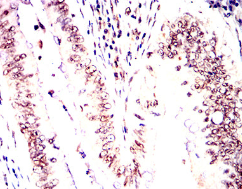

MRE11 Mouse Monoclonal antibody[4D2B6]

Immunogen :   Purified recombinant fragment of human MRE11 (AA: 182-582) expressed in E. Coli.

IHC    1/200 - 1/1000